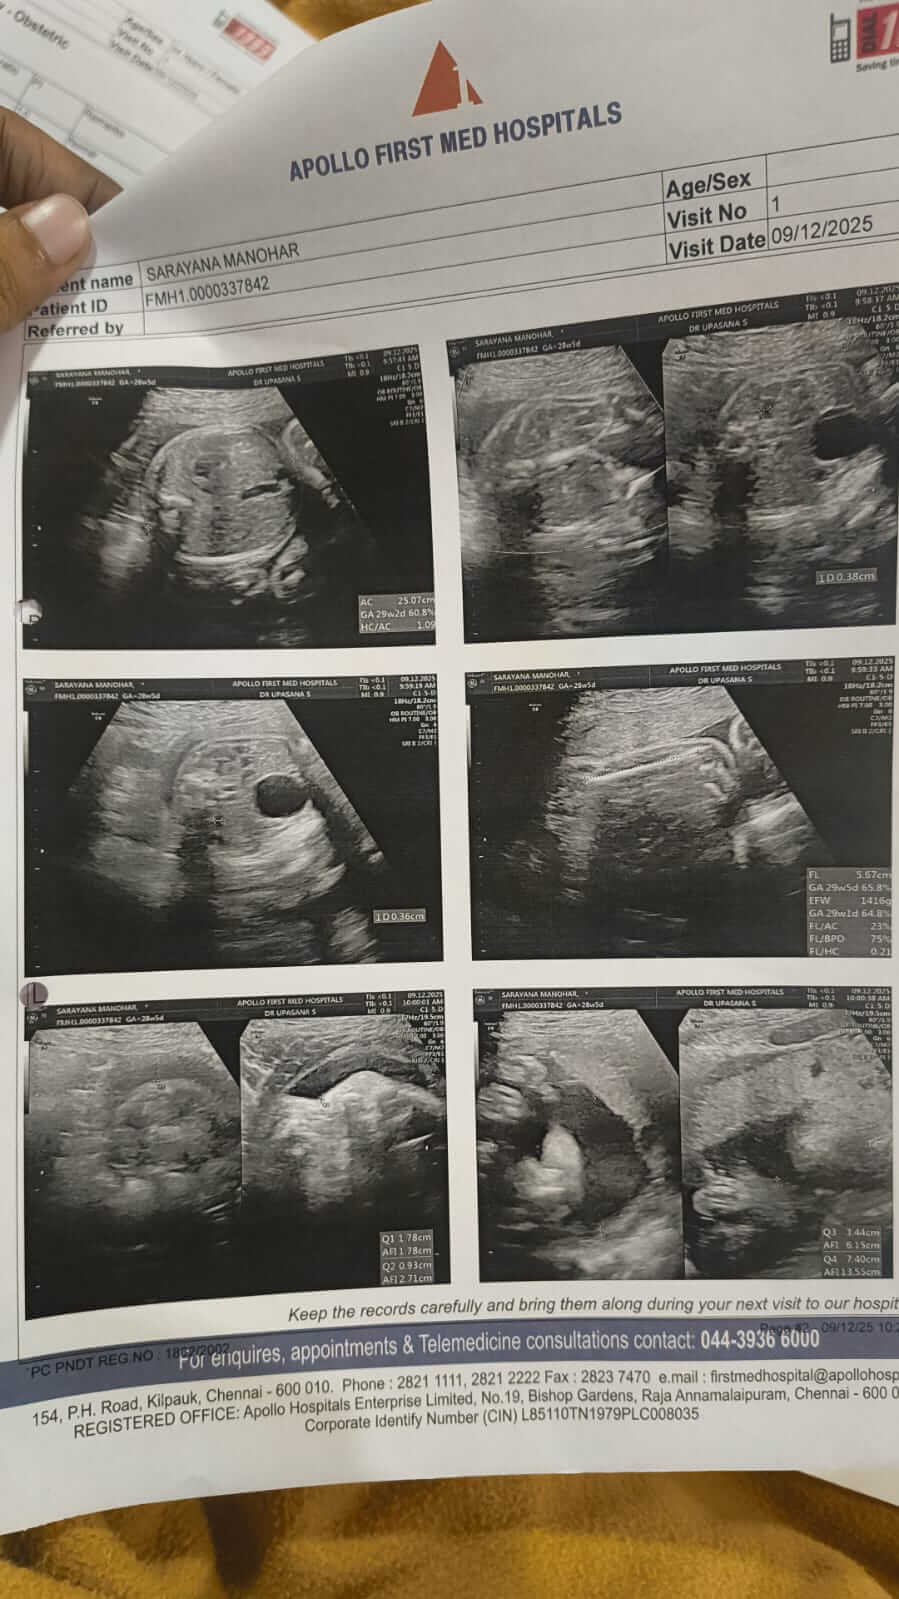

Saranya faced high-risk pregnancy complications and now, both my wife and my baby are fighting for their lives in the ICU.

What began as unbearable pain turned into an emergency surgery. I watched doctors rush her into the operating theatre, not knowing what was in store for my family. Our baby was born into machines, wires, and fear, taken straight into critical care. “They have to remain under strict medical observation and critical care,” said the doctors about my wife Saranya and our newborn baby.

Doctors have advised that both the mother and baby need continued ICU monitoring to survive.